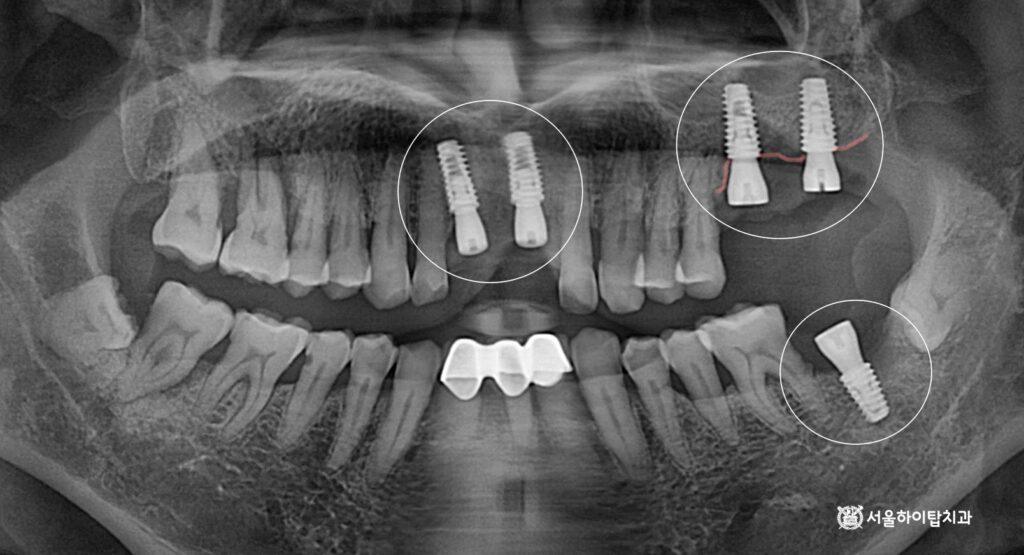

3. 수술 완료

상기 시뮬레이션을 기반으로

예측한 위치에 임플란트가

식립된 것을 확인할 수 있습니다.

특히 위턱의 경우

골 이식이 함께 이루어지면서,

임플란트가 골 내에서 안정적으로

자리 잡은 모습을 관찰할 수 있습니다.

이를 통해 수술 계획대로

심미, 기능 안정성이 확보된

상태임을 확인할 수 있습니다.

이후에는 치조골과 단단히 결합되는

골유착(osseointegration)을 거치게 됩니다.

간석역 치과 에서는 대략

4~6개월의 기간이 필요하다 말씀드리며,

환자의 골 상태나 초기 고정력에 따라

이 기간은 더 짧아질 수도 있습니다.